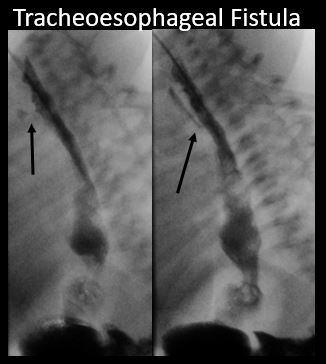

There is a tracheoesophageal fistula present. [Yes/No]